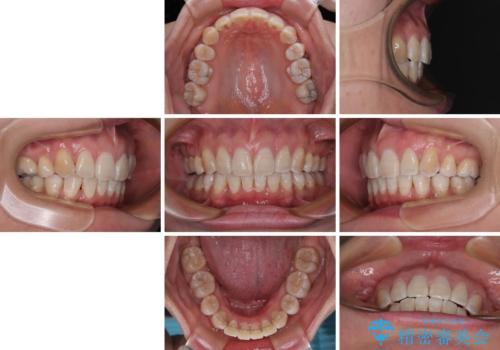

上顎前突で口が閉じにくい ワイヤー装置での抜歯矯正

- 上顎歯列の出っ歯を気にして来院された患者様です。

骨格的に上顎歯列が前方位にあり、口元の突出感が顕著な状態で、上下左右の第一小臼歯4本を抜歯して、ワイヤー装置での抜歯矯正を行うこととしました。

奥歯の咬み合わせ改善のために、アンカースクリューの使用と上顎左右第一小臼歯の抜歯のタイミングをコントロールして、理想的な咬み合わせに仕上げていくこととしました。

ご本人がびっくりするくらい劇的に口元の突出感が改善され、大変満足のいく仕上がりとなりました。